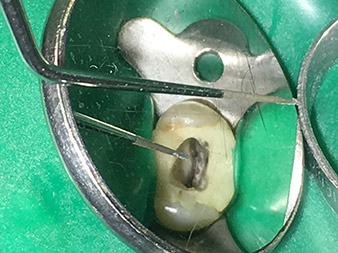

Neben effizienten Diagnose- und Behandlungsmethoden zählt der Einsatz neuester technischer Hilfsmittel und Instrumente zu den wichtigen Bausteinen einer erfolgreichen Patienten-Betreuung. Pro Woche kümmert sich Dr. Shahrad Nouraie Ashtiani zusammen mit seinem Team in der Praxis in Bremen (Deutschland) um bis zu zehn Endofälle. Die Forderung der Patienten nach einer möglichst schonenden Behandlung sowie guten Erfolgsprognosen bedeutet für den Zahnarzt und Weiterbildungsassistenten der Oralchirurgie mit Tätigkeitsschwerpunkt Endodontie eine tägliche Herausforderung.

Als Anwender des erweiterten W&H Instrumenten-Sortiments für die Ultraschall-Endodontie gelingt es Dr. Nouraie Ashtiani Wurzelkanalbehandlungen nicht nur effizienter, sondern vor allem mit weniger Belastung für den Patienten durchzuführen. Selbst schwierige Situationen werden vom Experten mühelos gemeistert. In einem Interview spricht der Endodontie-Spezialist über die besonderen Eigenschaften der W&H Instrumente und verweist auf mögliche Risiken in der Wurzelkanalbehandlung.

Dr. Nouraie: Besonders gerne arbeite ich mit der Spitze 1E. Diese eignet sich hervorragend zur Aktivierung der Spülflüssigkeit im Wurzelkanal. Durch die feine Gestaltung dieser Spitze kann man damit auch tiefe Kanalabschnitte erreichen und hier eine optimale Aktivierung gewährleisten.

Dank des materiell verstärkten Übergangs vom Arbeitsende bis hin zum Shaft konnte die Bruchgefahr dieses dünnen Instruments minimiert werden.

Dr. Nouraie: Ich habe mehrere Lieblingsspitzen. Meine absolute Lieblings- und Muss-Spitze ist die Spitze 1E. Diese findet ihre Indikation wirklich bei jeder Wurzelkanal-Behandlung, da mit dieser die Spülflüssigkeit aktiviert wird. Es ist bekannt, dass die Wurzelkanalspülung neben der Aufbereitung die wichtigste Komponente der Behandlung darstellt. Eine aktivierte Spülflüssigkeit dringt tiefer in die Dentin-Kanälchen ein und kann somit eine bessere Wirkung erzielen. Somit spielt die Aktivierung der Spülflüssigkeit für die Verbesserung der Qualität einer solchen Behandlung eine wichtige Rolle.

Dr. Nouraie: Der Einsatz von Ultraschallspitzen ermöglicht einen gezielten, schonenden und minimalen Substanzabtrag an der gewünschten Stelle (wie z.B. bei der Freilegung der Kanaleingänge, beim Abrunden des Kavitätenbodens und Freipräparieren von abgebrochenen Instrumenten oder Stiften sowie beim Bearbeiten der koronalen Kanalabschnitte).

Die Glättung und Abrundung der Kanalübergänge kann gezielter erfolgen als mit Hilfe von Bohrern. Insbesondere die Aktivierung der Spülflüssigkeit bringt enorme Vorteile, die durch andere Instrumente nicht gewährleistet werden kann. Mit Hilfe der Spezialinstrumente von W&H können ganz neue Indikationen minimalinvasiv durchgeführt werden, wie z.B. eine Revision von abgebrochenen Spitzen und Stiften.

Für alle Indikationen im Kanal sollten Sehhilfen in Form von Lupe oder noch besser in Form eines Mikroskops eingesetzt werden.